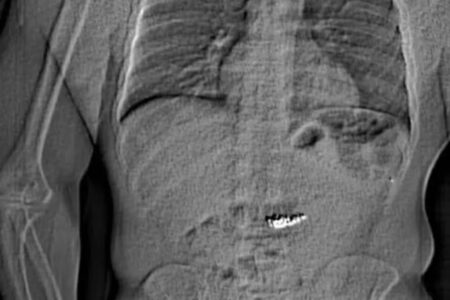

Uribe: atentado que chocou a Colômbia (Foto: Divulgação)

Colômbia: senador que sofreu atentado é operado com urgência

Polícia da Colômbia ainda não conseguiu descobrir quem ordenou o atentado, que foi executado por um rapaz de apenas 15 anos